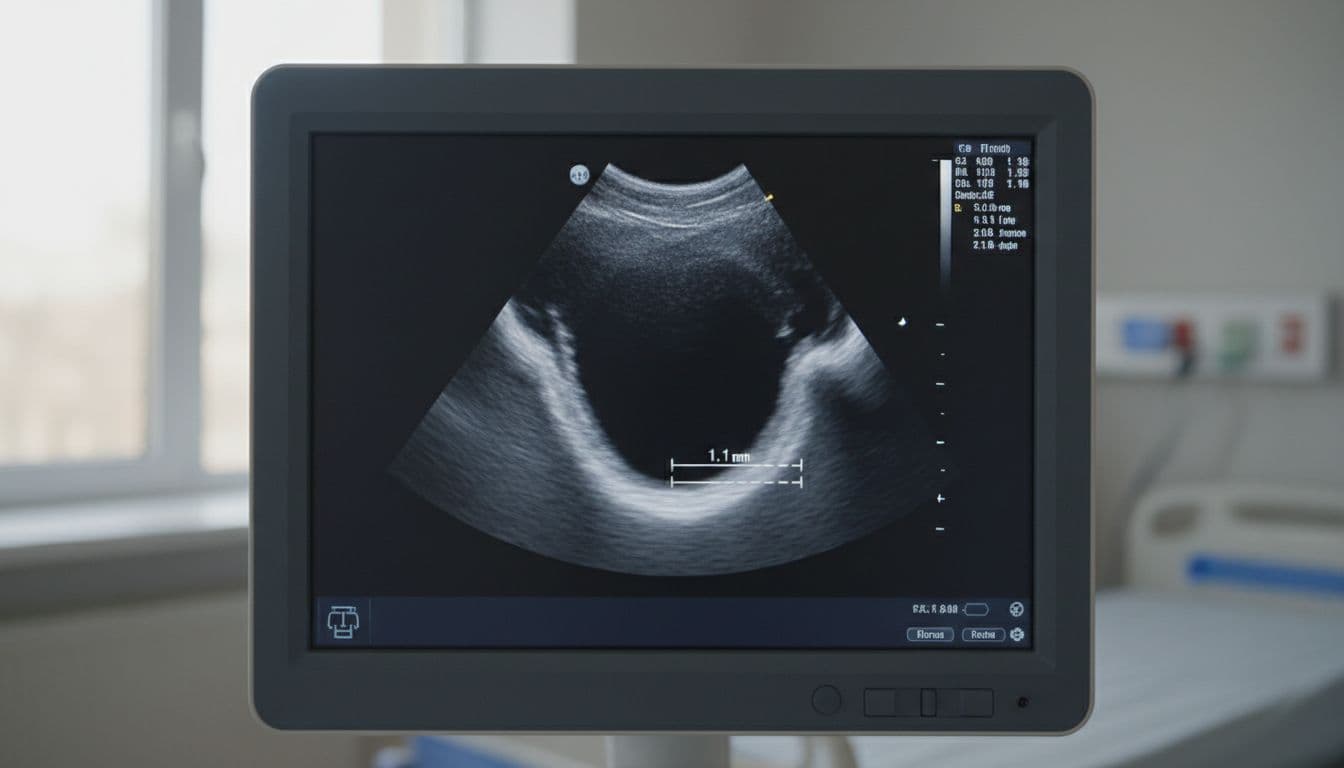

Think of the test as a flashlight on the neck arteries. A technician places gel on your skin and slides a small probe along the side of your neck. The scan uses sound waves, so there’s no radiation, no needles, and usually no recovery time.

It looks for a few key things. First, it checks whether blood flow is smooth or slowed. Next, it measures the artery wall and looks for plaque, which is a mix of fat, cholesterol, calcium, and scar-like material. In plain terms, plaque is like gunk collecting inside a pipe, only this pipe feeds your brain.